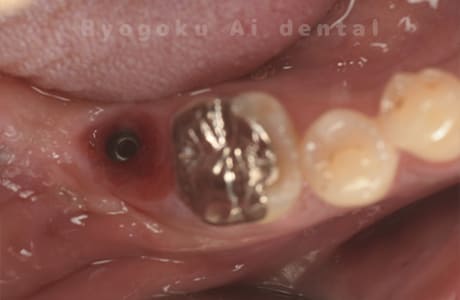

Case12

- 原因

- 左下7番歯牙破折

-

- 治療内容

- インプラント治療

- 治療費用

- 約600,000円

左下の奥歯が痛いとのことでご来院された患者様です。歯が完全に割れており、保存が不可能であったため、抜歯を行い、その際に骨に変わるお薬を入れ、十分な治癒を待ってからインプラント治療を行いました。経過良好で、大変満足されました。

<リスク・副作用>

治療後、痛みや違和感、出血、腫れなどが出る事があります。喫煙者、糖尿病などの方の場合、歯が生着しない場合があります。